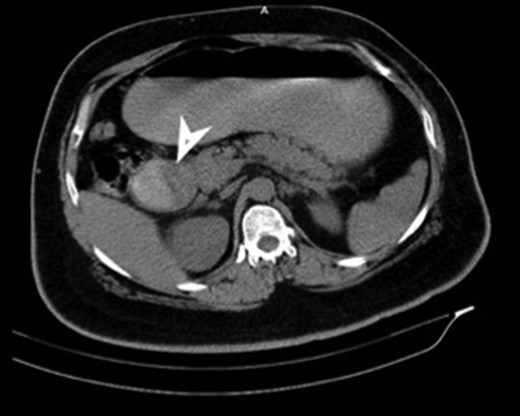

CT showing a polypoid lesion extending from the first part of the duodenum and projecting into the lumen of the second and third part.

| Case 2 | 44/M | 4 days | Malena, fatigue requiring blood transfusions | 60 × 45 mm2 mildly enhancing solid mass involving second and third part of duodenum with exophytic contour bulge likely polypoid lesion (Fig. 4) | A Large friable polypoidal lesion at junction of second and third part of duodenum | Non-specific chronic duodenitis with focal mild dysplasia | Transduodenal polyp excision (Fig. 5) | 2 | 1 | 5 |